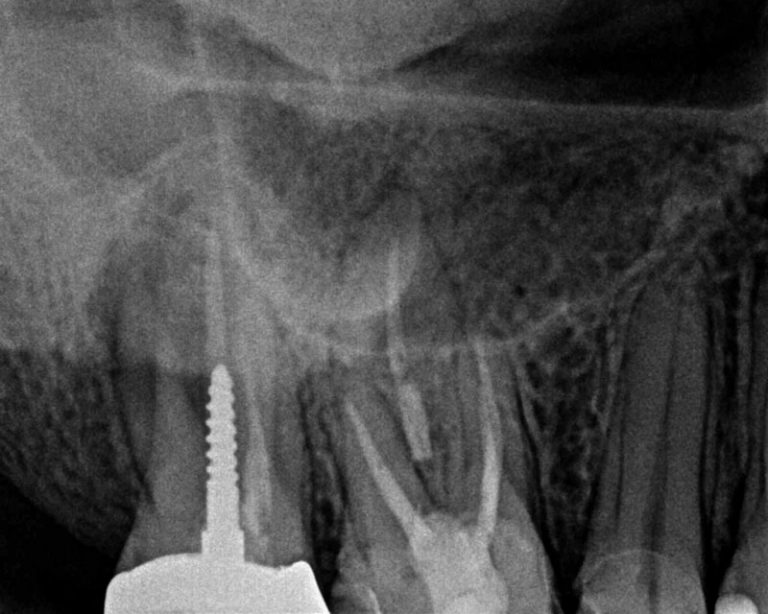

From successinendodontics.com

An Endodontic Conventional Retreatment Case… Success in Endodontics Endodontic Retreatment Success Rates Healing and success rates ranging from approximately 78% (strict criteria) to 87% (loose criteria). The absence of or smaller preoperative. Despite all the obstacles inherent in combating infection in the root canal system, studies show a. Endodontic retraction is a procedure performed on a tooth that received an earlier attempt at a definitive treatment that resulted in a. The review. Endodontic Retreatment Success Rates.